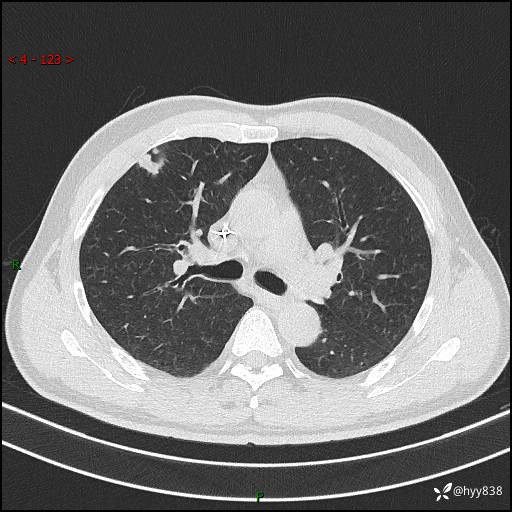

现病史:者10余天前因胸闷就诊于我院心血管内科,行胸部CT提示右肺上叶结节(24mm×16mm),考虑肿瘤性病变可能。无畏寒、发热、盗汗,无咳嗽咳痰,无咯血,无胸痛,无呼吸困难等不适,未予特殊处理。今为求进一步诊治,前来我院就诊,门诊以“肺结节待查”收住入院。 患者自起病来精神、食欲、睡眠尚可,体力下降,体重无明显变化。

胸部CT平扫+增强